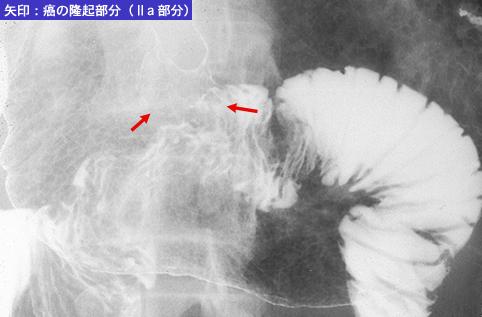

疾患(病理主体)の分類悪性上皮性腫瘍/印環細胞癌

部位(臓器別)胃(部位)/胃角

検査方法X-P

腫瘍の肉眼分類0型(表在型)/IIc型(IIc+IIa)

病変の最大径(ミリ)40以上

腫瘍の深達度sm